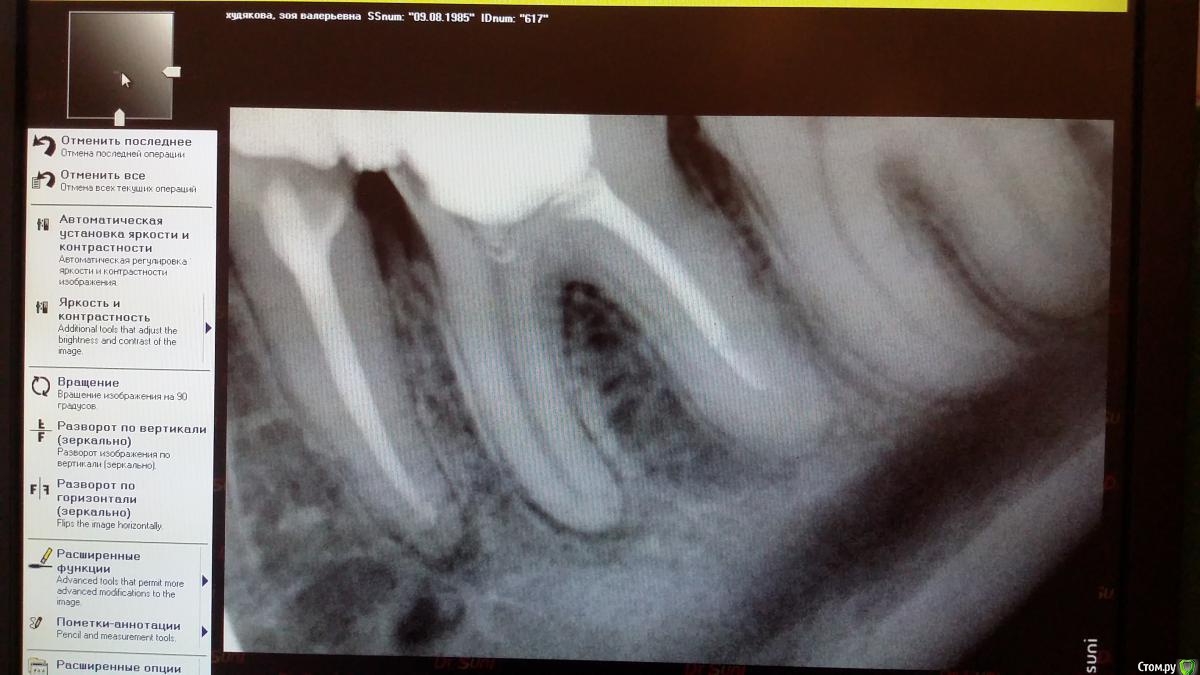

Recive Опубликовано 16 февраля, 2015 Автор Поделиться Опубликовано 16 февраля, 2015 Там была ступенька в дистальном канале ((( Не много вывел , при конденсации, силлера. 1 Ссылка на комментарий

Recive Опубликовано 16 февраля, 2015 Автор Поделиться Опубликовано 16 февраля, 2015 Нужно. Снимок после пломбировки покажитеснимок просили. Ссылка на комментарий

Л Ю С Я Опубликовано 16 февраля, 2015 Поделиться Опубликовано 16 февраля, 2015 снимок просили.По Вашему мнению что в дистальном за апексом? Ссылка на комментарий

Recive Опубликовано 17 февраля, 2015 Автор Поделиться Опубликовано 17 февраля, 2015 По Вашему мнению что в дистальном за апексом?Там была ступенька в дистальном канале ((( Не много вывел , при конденсации, силлера. Ссылка на комментарий

Л Ю С Я Опубликовано 17 февраля, 2015 Поделиться Опубликовано 17 февраля, 2015 Ступеньку желательно обойти . Хотя дольше похоже на боковое отверстие имхо Ссылка на комментарий

Recive Опубликовано 17 февраля, 2015 Автор Поделиться Опубликовано 17 февраля, 2015 Ступеньку желательно обойти . Хотя дольше похоже на боковое отверстие имхо.04 протейпер f1 yellow Зуб не болел и никак не проявлял себя. Принято решение заплозапломбировать.собственно фото каналов после абтурации.скажите пожалуйста, а медиальные каналы по апексу нормально? Очень редко получается 1мм не проталкивать за апекс. Хотя по контрольной рентгенограмме с мастер-шмастер-штифтом все чики-пуки. Ссылка на комментарий

Л Ю С Я Опубликовано 17 февраля, 2015 Поделиться Опубликовано 17 февраля, 2015 Если стоп упор сформирован , апекс не на дырявите, мастер штифт правильно подобран,ничего не должно при латералке выводится. Может силера много берете, выбор спредера, как давите и др- все имеет значение. Соблюдайте РД , несколько раз перемеривайте Ссылка на комментарий